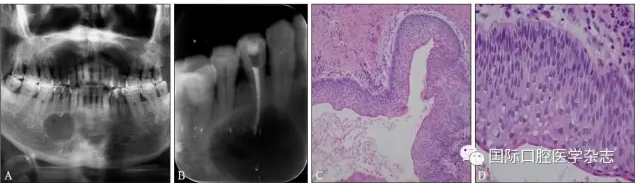

典型病例3 患者右下頜長包1月,臨床初診為44牙根尖周囊腫,治療期間反復(fù)換藥,伴右下頜脹痛,根管充填后轉(zhuǎn)診外科行根尖囊腫刮治A術(shù),術(shù)后病理示:右下頜骨KCOT伴感染(圖3)。

A:術(shù)前全景片,43—45根方透射影像,邊緣可見骨白線;B:術(shù)前充填根尖片;C、D:蘇木精-伊紅染色切片,示腫瘤襯里上皮表面為波浪狀的不全角化層,基底層細胞柵欄狀排列,細胞核遠離基底膜,C圖 × 100,D圖 × 400。

圖 3 右下頜骨KCOT

Fig 3 KCOT in the rightmandible